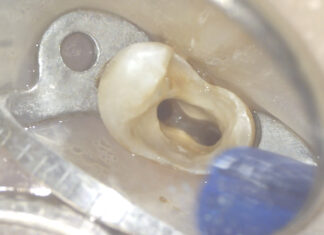

Ritrattamento canalare. Rimozione di 2 perni in fibra con tecnica ultrasonica

Il ritrattamento canalare è una procedura che si attua al fine di risolvere le problematiche endodontiche in essere e ha come scopo quello di...